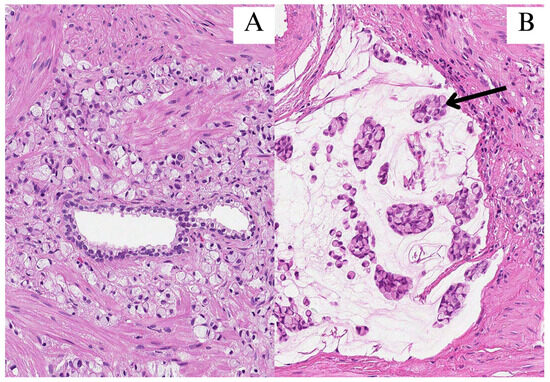

2. Case Report